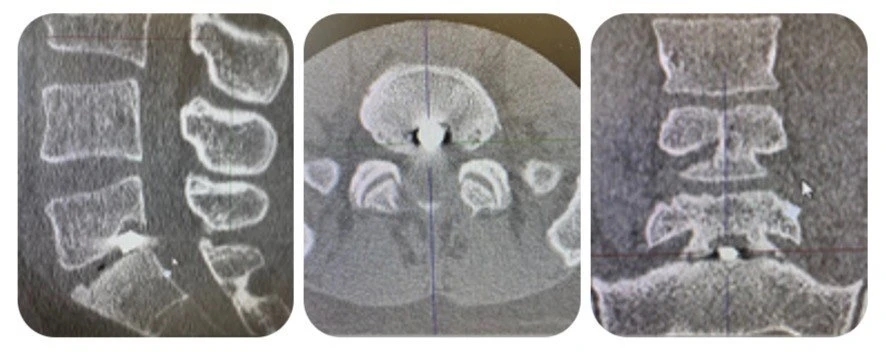

При повторном обследовании был обнаружен металлический осколок в межтеловом промежутке по срединной линии на уровне L5 и S1 позвонков. Инородное тело прошло между дужками сзади по краю фасеточного сустава.

Традиционно для удаления таких инородных тел применяются классические методики со скелетированием структур заднего опорного комплекса. Такие манипуляции сопровождаются большой операционной травмой, значительной интраоперационной кровопотерей, длительным реабилитационным периодом и риском инфекционных осложнений. Минимально-инвазивная монопортальная эндоскопическая методика в этом случае была нереализуема по техническим причинам из-за крупных размеров осколка, его центрального расположения и анатомических особенностей уровня L5-S1.

Тогда специалисты госпиталя решили применить бипортальную эндоскопическую методику. Операцию выполняли через два мини-разреза по 0,7 см на уровне ранения. Под контролем флюороскопии сформированы порты — один для эндоскопа и второй для рабочего инструмента.